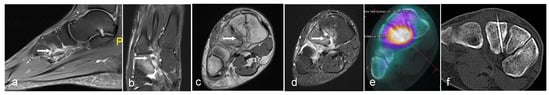

Figure 5. Axial T1 (a), STIR (b) showing aneurysmal bone cyst of fibula (arrow) treated with sclerotherapy under CT guidance (c,d).

The cyst is typically accessed using an 11 G bone biopsy needle. If the lesion is multiloculated, the needle is agitated to break up the septations to facilitate communication and its contents are aspirated. The position is confirmed with the injection of iodinated contrast which also has the benefit of confirming no intravascular communication or leak into other adjacent structures is present as also described in the existing literature [28,29]. If the lesion cannot be completely opacified, further punctures may be required. Once satisfactorily opacified, the sclerosant is injected and subsequently aspirated to minimise the risk of leakage. This allows the lesion to consolidate or involute over successive procedures (Figure 4 and Figure 5).

Sclerotherapy advantageously does not suffer from the risks to adjacent tissues and skin seen with the thermoablation techniques described above. Complication rates are low but sclerosant leakage or injection into vascular structures is a potential risk which can lead to embolism and tissue necrosis. Perhaps the biggest drawback is that repeat procedures are frequently necessary, particularly for larger lesions resulting in substantial time and resource allocation [30,31,32].